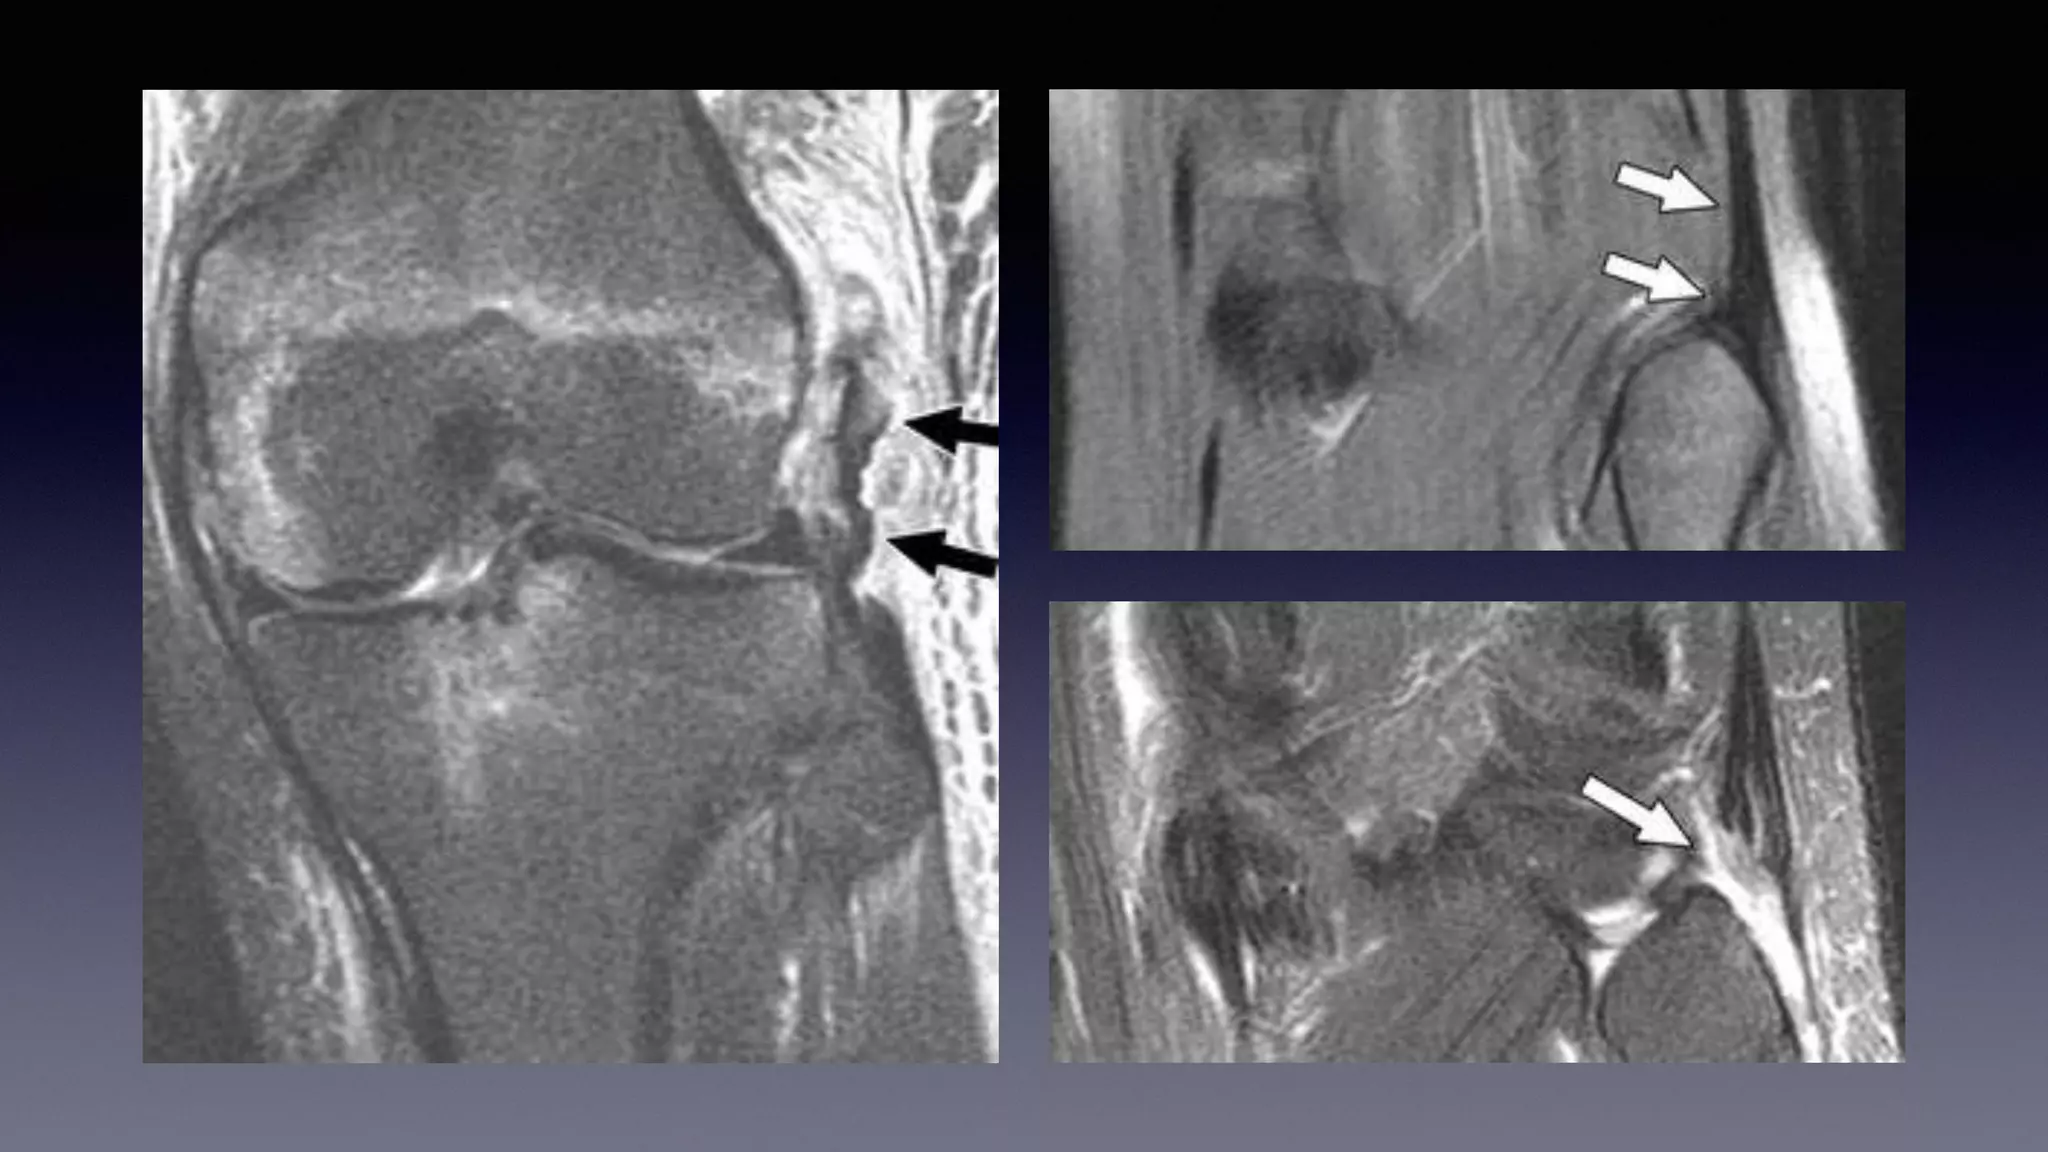

This document discusses using MRI to diagnose ligament injuries in the knee. It begins with an overview of MRI anatomy of the knee and expected pathology. It then discusses specific ligaments like the ACL, PCL, MCL and LCL. For the ACL, it shows images of acute tears, chronic tears and intrasubstance tears. It emphasizes knowing the knee anatomy well and correlating any abnormalities seen with clinical findings in order to apply the appropriate treatment.